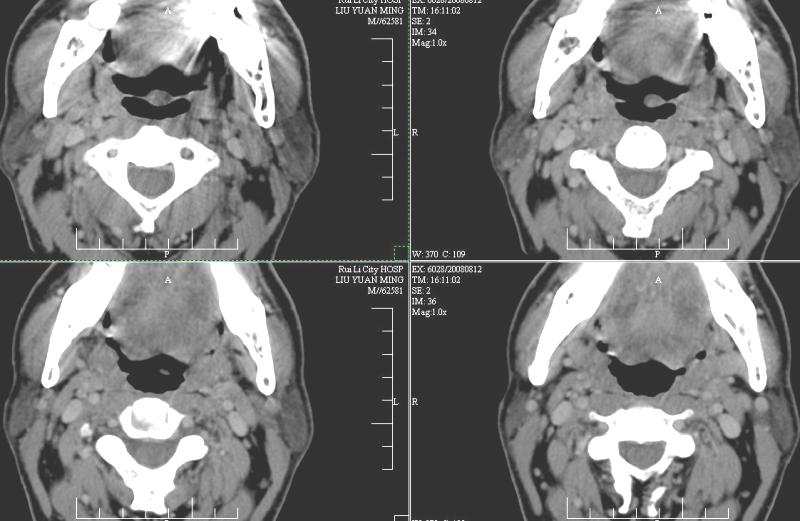

以下是引用ydx_74在2008-8-12 22:09:00的发言:[br]不考虑鼻咽癌。没有淋巴结肿大,没有颅底骨质破坏,咽隐窝、咽鼓管咽口存在,咽旁间隙清楚,平扫ct值34hu,增强动脉期81hu,实质期约85hu,增强幅度达50多,除外增强时机没有掌握好因素,可以考虑鼻咽纤维血管瘤吗?

以下是引用卜一在2008-8-13 8:07:00的发言:[br][br] 鼻咽部新生物,性质待定(不排除鼻咽癌可能);建议行鼻咽镜检查(活检)。 [br]支持!